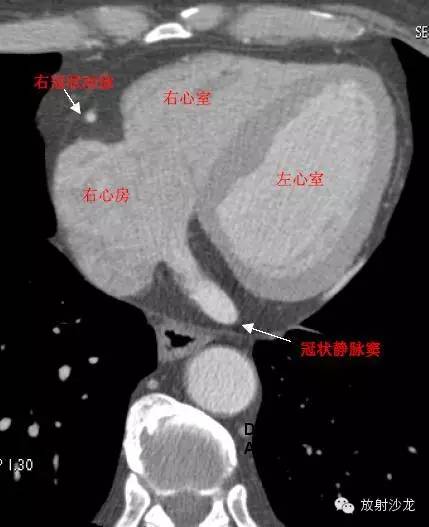

RA -Right Atrium右心房

LV -Left Ventricle左心室

RV -Right Ventricle右心室

RCA -Right Coronary Artery 右冠状动脉

RAA –Right AtrialAppendage右心耳

CS -Coronary Sinus冠状窦